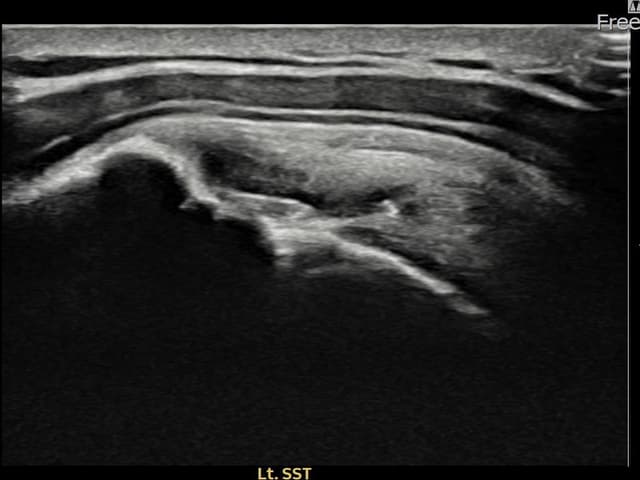

[経過期間: 23.07.31~23.09.27]

[縫縮術] 超音波検査にて左 棘上筋腱 부착부 광범위 部分断裂(13mm × 5mm (腱厚の約65%欠損))を確認。縫縮術施行後、腱の連続性が回復し、日常生活に復帰されました。